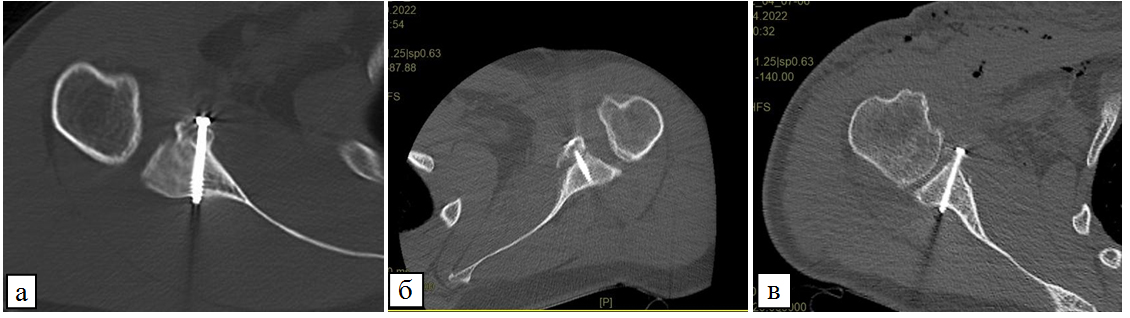

По данным предоперационного КТ-исследования, средняя величина предоперационного дефекта суставного отростка лопатки составила 18,6 % относительно противоположного сустава (0–34 %). В 62 случаях было выявлено костное повреждение Банкарта, в 10 – костная эрозия. В 4 случаях костный дефект отсутствовал. При анализе послеоперационных КТ, согласно классификации Zhu Y. с соавт., резорбция костного блока трансплантатов произошла в 49 случаях (64,4 %), из них 1-й степени – в 27 (55,1 %), 2-й степени – в 16 (32,6 %) и 3-й степени – в 6 (12,2 %) случаях (рис.).

Рис. Резорбция костного блока трансплантата 1-й степени (а), 2-й степени (б), 3-й степени (в)

Более выраженная резорбция наблюдалась в верх- ней части трансплантата вокруг фиксирующего его верхнего винта. Средняя величина предоперационного дефекта суставного отростка лопатки составляла 20,7 % при 1-й степени резорбции, 18,9 % – при 2-й сте- пени, 11,4 % – при 3 степени резорбции (табл. 2). Рецидивов нестабильности не возникало, однако у 4 пациентов наблюдали положительный тест предчувствия.